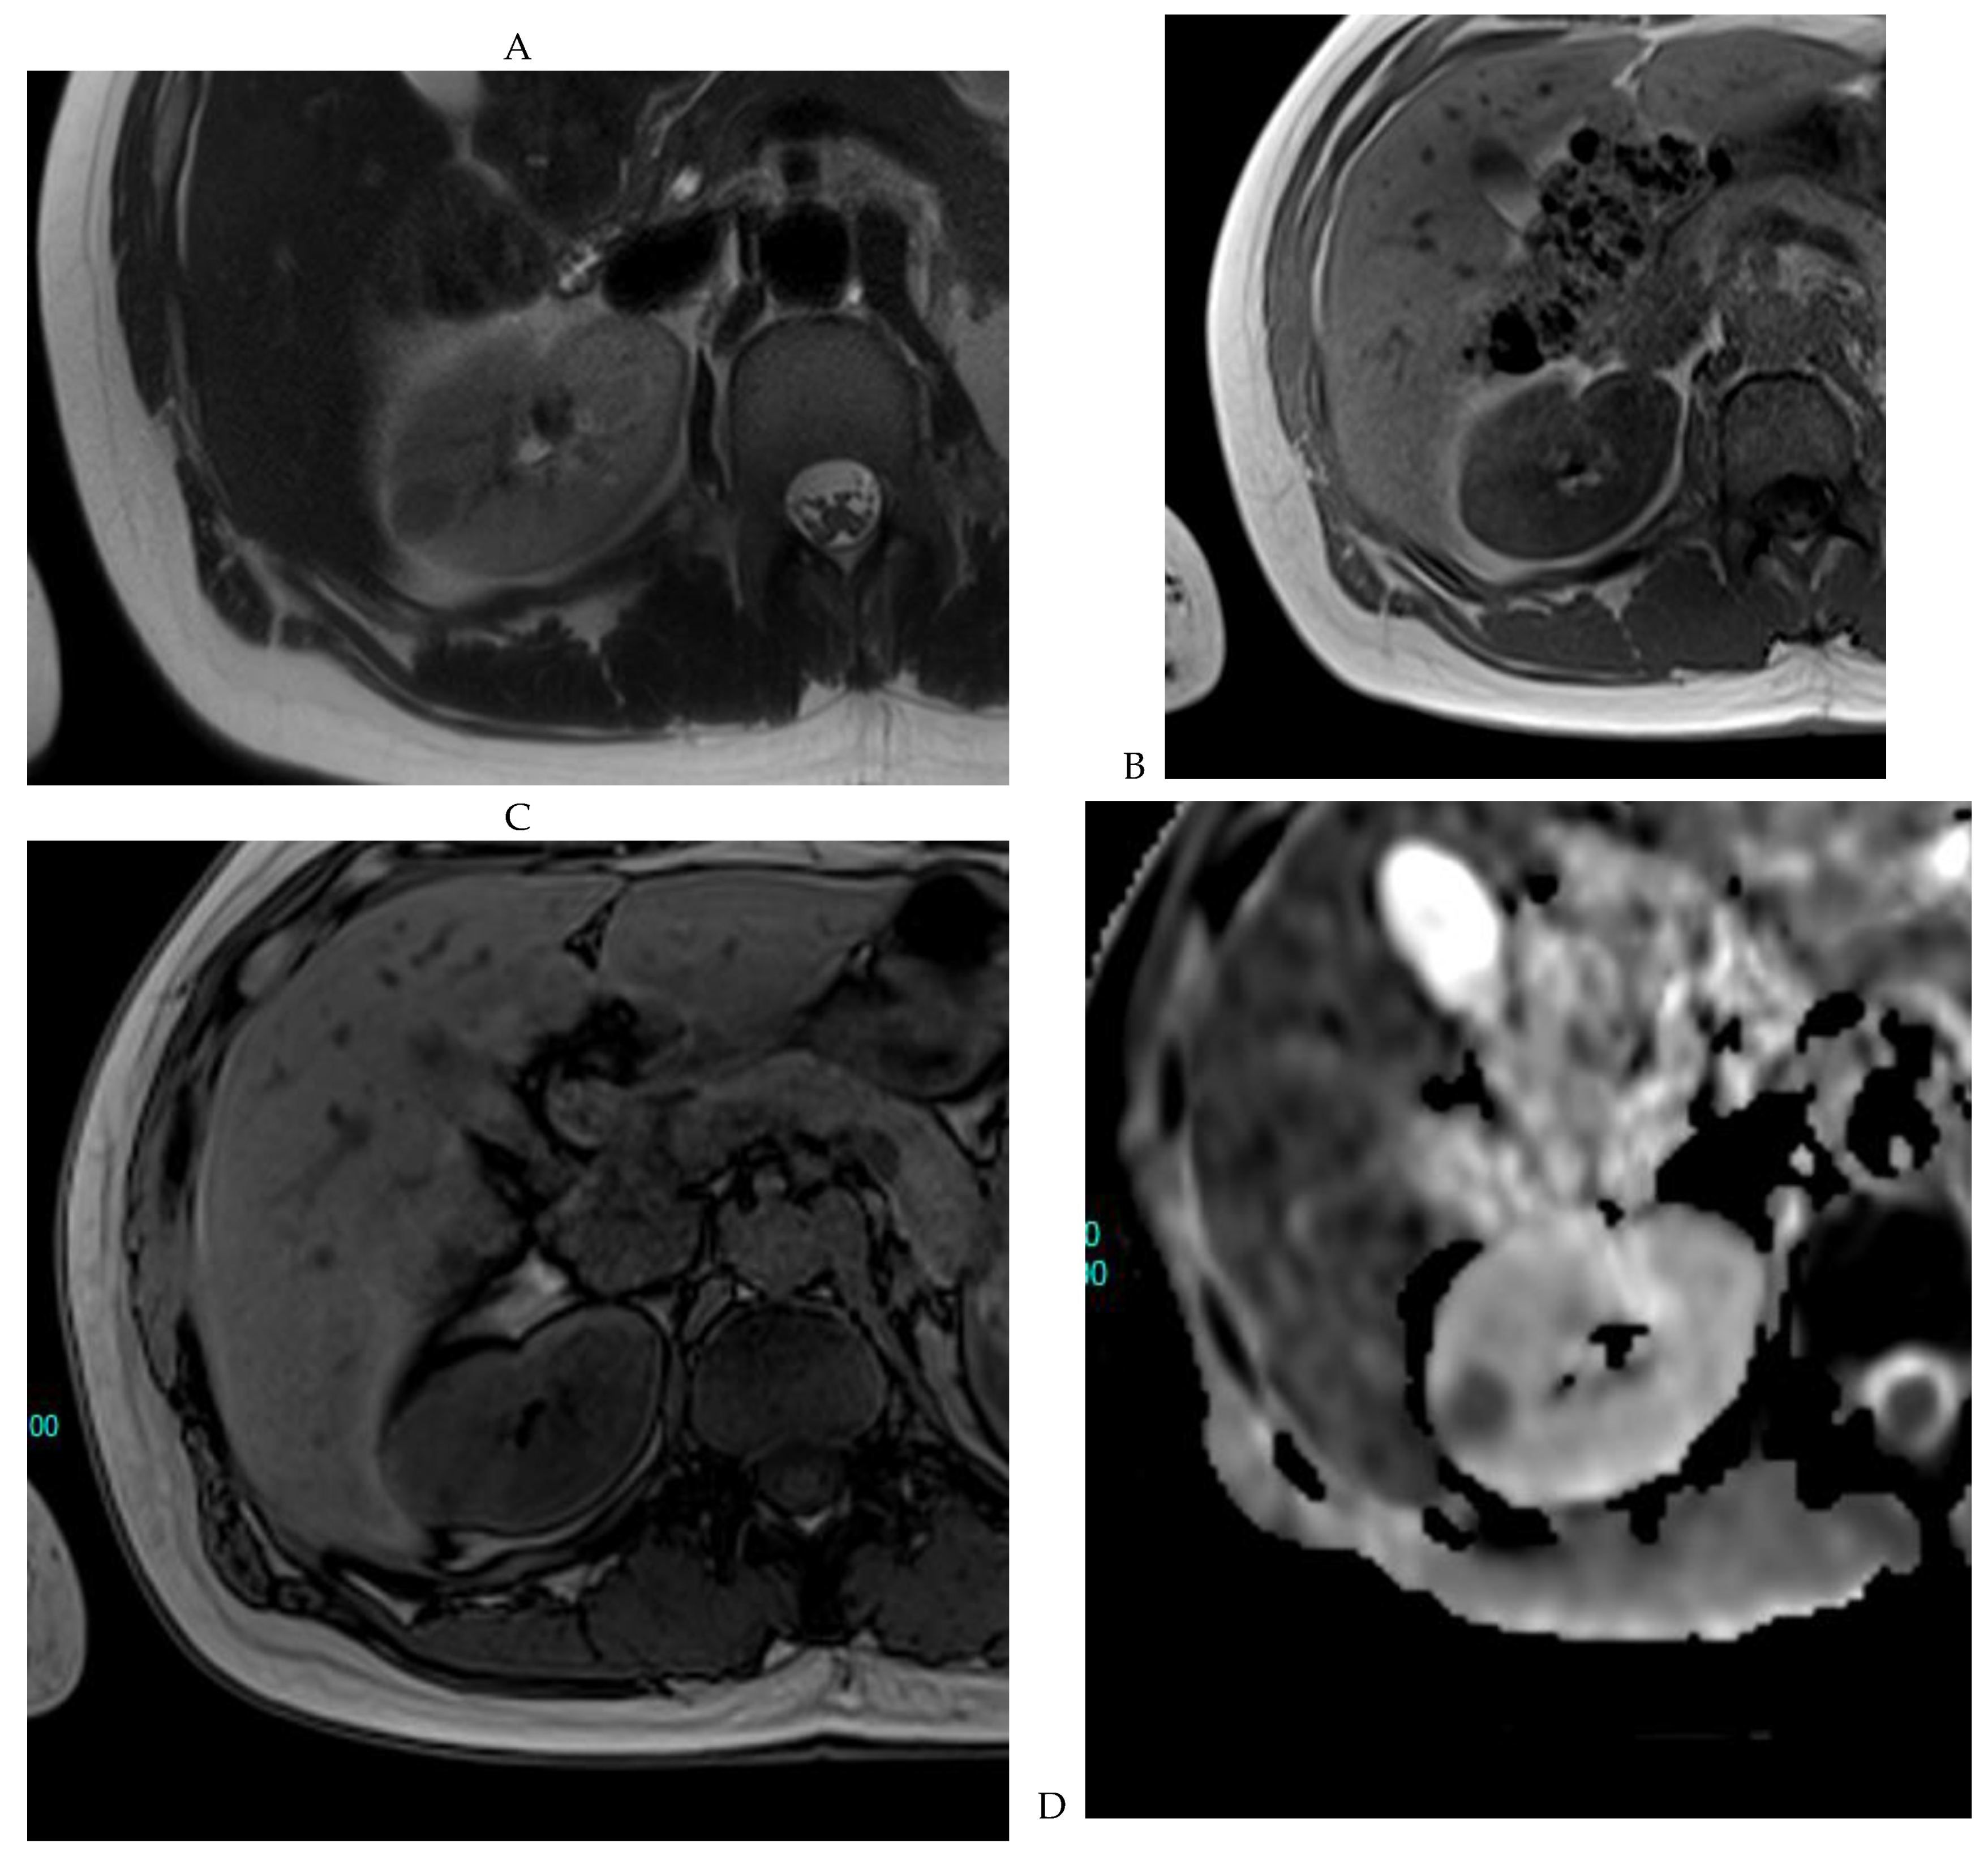

Figure 7.

Papillary renal cell carcinoma in the right kidney of a 75-year-old-woman. (A) Axial T2-weighted fast SE image shows a homogeneous 1.8 cm mass in the posterolateral region of the right kidney, with a lower SI compared to renal parenchyma. Transverse in-phase (B,C) opposed-phase MR images do not show a significant signal loss on the opposed-phase image. (D) The ADC map shows restriction of tumor diffusion into the renal mass. Transverse nonenhanced (E) and gadolinium-enhanced T1-weighted gradient-echo spoiled MR images in (F) corticomedullary, (G) nephrographic, (H) and delayed phase images show progressive enhancement without washout; the mass is hypovascular compared to the renal cortex.